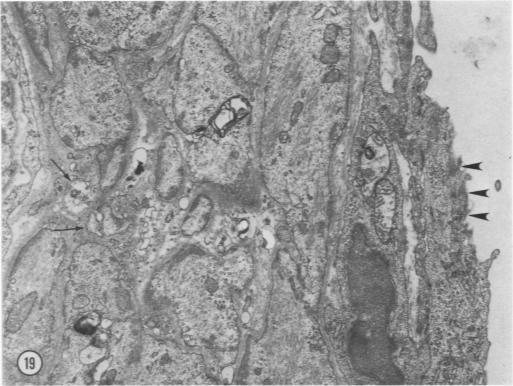

Acute hypertension has been produced in rats by the intravenous infusion of angiotensin amide for 4 hours. Both control and hypertensive animals were injected intravenously prior to sacrifice with either horseradish peroxidase (HRP) or colloidal carbon. Epicardial arteries and blocks of ventricular myocardium containing intramyocardial arteries and arterioles have been processed for electron microscopy. HRP appears to penetrate the endoethelium of epicardial arteries from control animals within vesicles that bypass endothelial junctions and empty into interendoethelial clefts. Peroxidase does not traverse the endothelium of intramural arteries and arterioles of controls over the 10-minute period of observation. There is acceleration of lateral vesicular transport in the endothelium of epicardial arteries after angiotensin infusion and direct permeation of interendothelial clefts of intramural arterial vessels. Medial fragmentation and more extensive necrosis are observed in intramyocardial but not in epicardial arterial vessels. Foci of myocardial damage resembling irreversible ischemic or anoxic injury followed by reflow are described. It is suggested that the increased permeability of epicardial arteries may be due to elevated pressure, while the altered permeability and vascular lesions of intramural arteries and arterioles are more readily attributable to the vasoconstriction produced by angiotension. The vascular and myocardial lesions are also discussed in relation to the regional actions of angiotensin on the coronary circulation and known effects of this vasoactive peptide on myocardium.